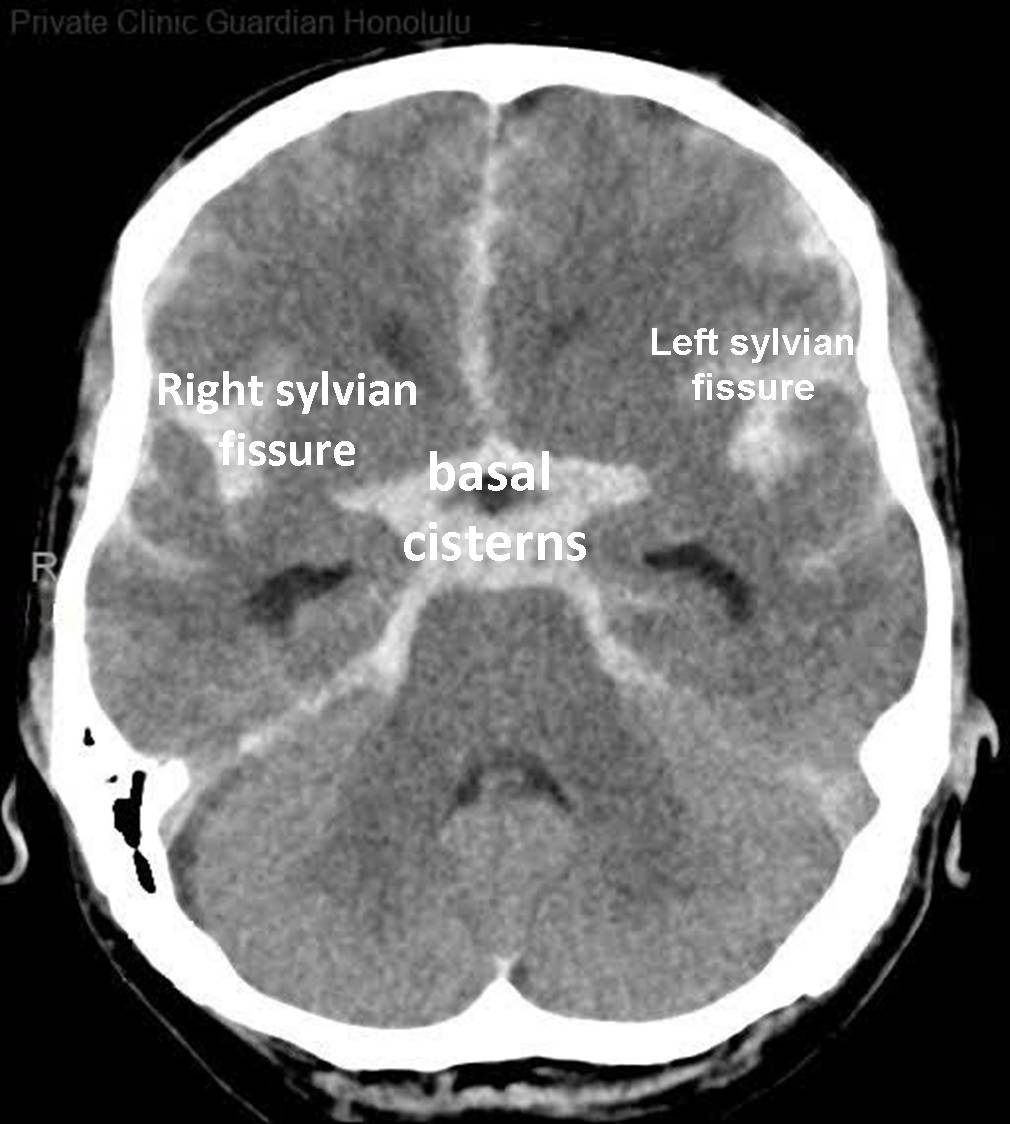

CT features of SAH

‘Dancing man’ around circle of willis

Hyperdense in basal cistern, lateral fissues, L and R sylvian cistern